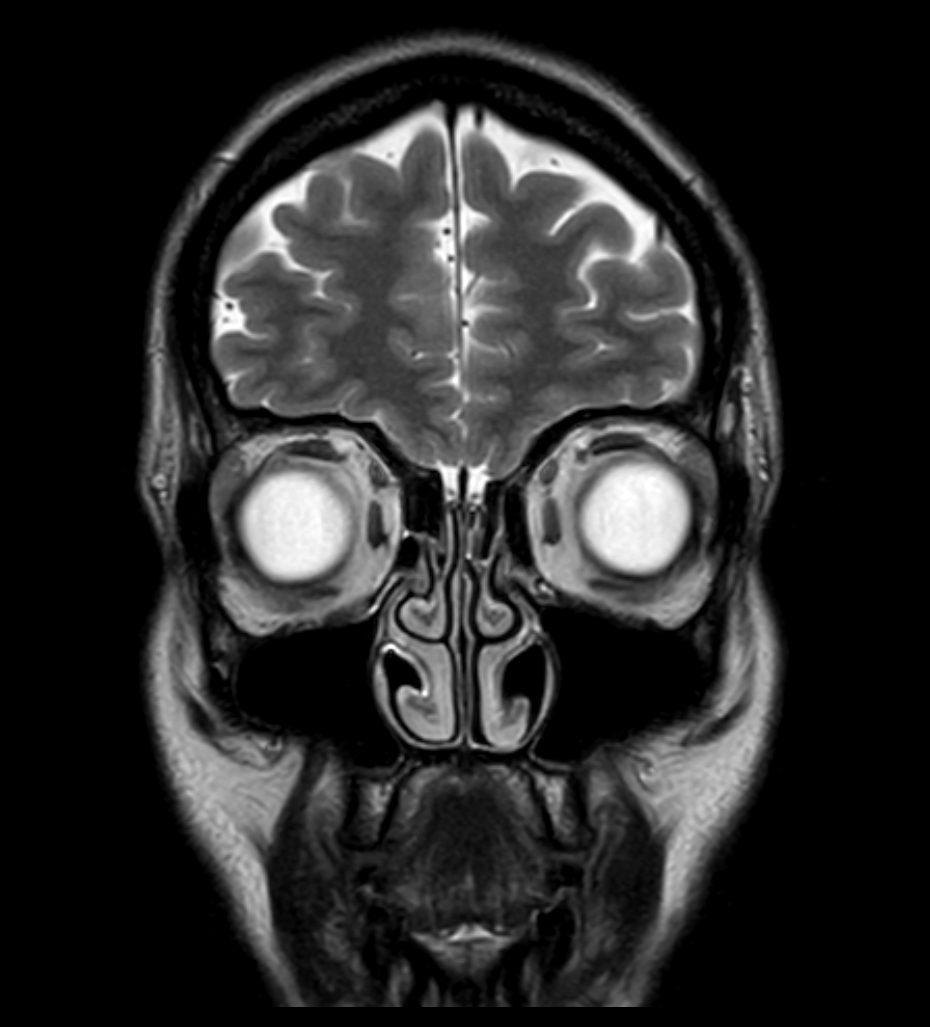

T2w TSE - mDIXON XD (In Phase)

T2w TSE - mDIXON XD (Water only)